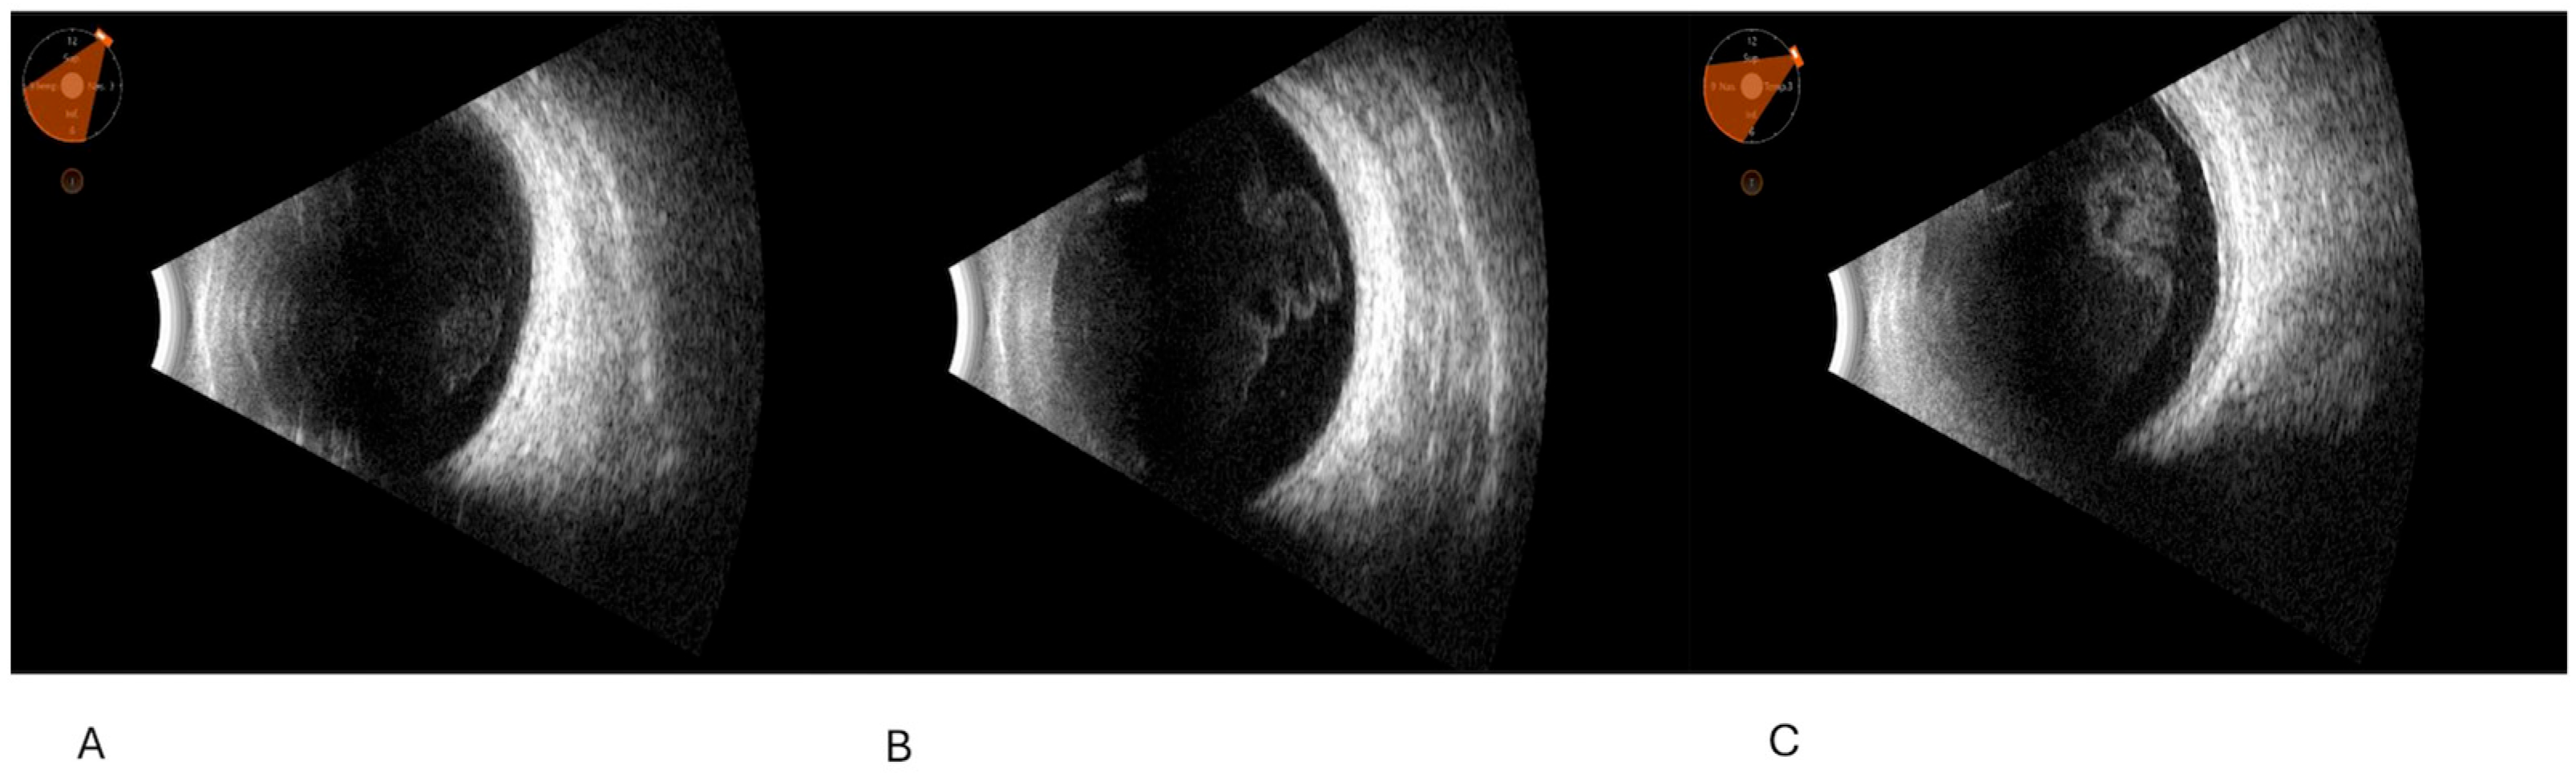

Solid tumor associated with vitreous and/or retina and/or choroid and/or extrinsic muscles and/or other orbital structures: This was typical of neoplasms, such as intraocular or orbital lymphoma, melanomas (associated with vitreous corpuscles, especially in the necrotizing form), metastasis, retinoblastoma, leukemia, and other lymphoproliferative conditions. Some solid tumors may have growth toward the vitreous. These types of tumors arose in differential diagnosis with foreign bodies, which instead may be suspended in the vitreous or lying on the posterior profile, characterized by sonographic posterior shadowing.

Representative images are given in Figure 1, Figure 2 and Figure 3.

Figure 3. Complete annular hematological cellular infiltration of the tenon capsule and sclera, with a “sleeve-like” appearance, also involving the posterior pole (plasmacytoma); none of vitreous abnormalities are shown.